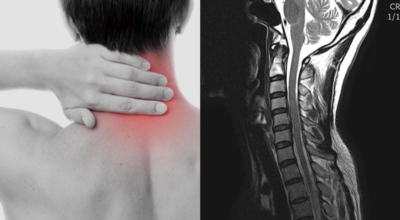

목에 통증이 발생되는 것은 목디스크 증상 중에서 제일 처음 발생하는 증상이죠. 목이 계속 뻐근한 느낌이 들뿐만 아니라 고개를 살짝만 돌리더라도 통증이 느껴질 때가 있으며 심한 경우에는 아예 머리를 돌리지 못하게 되는데요.

4. 목디스크 증상 - 어깨 통증

목디스크의 또 다른 증상 중에 하나는 바로 어깨 통증이죠. 목부터 시작된 통증이 어깨까지 넘어가게 되는데 이는 목과 어깨의 신경이 연결되어 있기 때문이죠. 목에 통증이 먼저 생기고 연결된 어깨의 신경에 부담이 가해지고 자극을 받아 어깨에 통증이 발생되는 것으로 보입니다.

목디스크 증상이 나타날때 빨리 발견하여 비수술 치료를 받고 꾸준히 관리하는 것이 베스트이죠. 목디스크 환자 중 수술을 진행하는 환자는 2% 미만으로 현저히 적다고 해요. 수술을 진행하는 경우는 감각이 느껴지지 않는 마미증후군이나, 한쪽 다리가 눈에 띌 정도로 야윈 경우에만 진행하므로 올바른 자세 교정만으로도 충분히 호전될 수 있는 질병이죠. 목에 연관된 검사는 MRI나 CT를 이용해요. 그러나 전자의 경우 비용이 굉장히 비싸기 때문에 디스크 증세가 확실하다고 생각될 경우에만 선택적으로 하고 의무적으로 하는 건 아니니까 비용에 대해선 부담을 가지지 마시길 바래요.